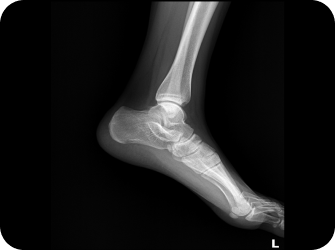

발목염좌

습관성 발목염좌는 일상생활이나 운동을 할 때 발목을 자주 접질리는 증상입니다.

발목관절을 지지하고 있는 인대에 비정상적인 외부 힘이 가해져 손상되거나 과하게 긴장되어 심한 경우에는 인대가 끊어진 상태를 말합니다.

원인

• 발목을 심하게 비틀리거나 접질렀을 때

발목 관절을 지지하는 인대들의 손상으로,

만성 발목염좌로 이환될 수 있습니다.

발목터널증후군

발목 안쪽 복사뼈와 발뒤꿈치를 잇는 굽힘근지지띠의 안쪽 공간을 발목터널이라고 합니다.

이 부위가 다양한 원인에 의해 좁아지게 되면, 신경을 압박하게 되는데 이때 감각이 둔해지거나 전기가 통하는 듯 느끼는 증상입니다.

• 기능성평발

• 발목의 잦은 염좌

• 골절

• 타박상에 의한 손상

• 발목의 신경을 압박하는 종양이나 낭종

• 과체중과 비만